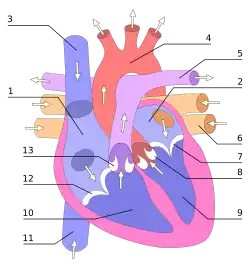

O coração bombeia sangue ao ritmo determinado por um grupo de células marca-passo situadas no nódulo sinoatrial. Estas células produzem uma corrente elétrica que percorre o nódulo atrioventricular e o sistema de condução elétrica do coração, provocando a sua contração a um ritmo regular. O coração recebe o sangue pobre em oxigénio da circulação sistémica, que entra na aurícula direita pelas veias cava superior e inferior e daí passa para o ventrículo direito. Do ventrículo direito o sangue é bombeado para a circulação pulmonar, onde liberta dióxido de carbono e recebe oxigénio. O sangue oxigenado regressa então à aurícula esquerda e daí passa para o ventrículo esquerdo, onde é bombeado para a artéria aorta, entrando novamente na circulação sistémica.[8] Em repouso, o coração bate a um ritmo de aproximadamente 72 batimentos por minuto.[9] O exercício físico aumenta temporariamente o ritmo cardíaco, embora a longo prazo contribua para diminuir o ritmo em repouso e seja benéfico para a saúde do coração.[10]

O sistema cardiovascular, ou sistema circulatório, é constituído pelo coração e pelos vasos sanguíneos. O coração, embora seja um órgão único, pode ser descrito como um conjunto de duas bombas que fazem circular o sangue de forma contínua em dois circuitos: a circulação sistémica e a circulação pulmonar. Os vasos sanguíneos transportam o sangue rico em oxigénio e nutrientes para todas as células do corpo.[14]

O coração atua de forma semelhante a uma bomba hidráulica, fazendo com que o sangue circule no sistema cardiovascular de forma contínua. O sistema cardiovascular divide-se em dois circuitos distintos: a circulação pulmonar, que transporta o sangue para os pulmões onde se dão as trocas gasosas, e a circulação sistémica, que fornece sangue a todos os órgãos do corpo, incluindo aos pulmões e ao próprio coração.[14]

O coração esquerdo irriga a circulação sistémica, bombeando sangue arterial rico em oxigénio para a maior artéria do corpo, a artéria aorta. A aorta ramifica-se em inúmeras artérias que levam o sangue a todas as células do corpo. Nas células, o sangue liberta oxigénio e nutrientes e recolhe dióxido de carbono e outros resíduos metabólicos. O sangue venoso, pobre em oxigénio, regressa ao coração pelas veias.[14][15][7]

O coração direito irriga a circulação pulmonar. A aurícula direita recebe o sangue venoso da circulação sistémica, pobre em oxigénio. Daí passa para o ventrículo direito, onde é bombeado para a artéria pulmonar e entra na circulação pulmonar. Nos pulmões, o sangue liberta o dióxido de carbono e recebe o oxigénio inalado pelo sistema respiratório. O sangue rico em oxigénio regressa então ao coração esquerdo pelas veias pulmonares. Entra pela aurícula esquerda e daí passa para o ventrículo esquerdo, onde é novamente bombeado para a circulação sistémica, repetindo-se o ciclo. As válvulas cardíacas fazem com que o sangue flua em sentido único e ajudam a manter a pressão necessária.[14][15][7]

Circulação do sangue nas cavidades

O coração direito recolhe o sangue desoxigenado a partir de duas grandes veias, a veia cava superior e a veia cava inferior. A veia cava superior recolhe o sangue proveniente das regiões do corpo acima do diafragma e descarrega-o na parte superior e posterior da aurícula direita. A veia cava inferior recolhe o sangue proveniente das regiões do corpo abaixo do diafragma e descarrega-o na parte posterior da aurícula, por baixo da abertura da veia cava superior. Imediatamente por cima do orifício da veia cava inferior encontra-se o orifício do seio coronário. O seio coronário descarrega na aurícula direita o sangue desoxigenado da circulação coronária. O sangue acumula-se na aurícula direita de forma contínua. Quando a aurícula se contrai, o sangue é forçado a passar para o ventrículo direito através da válvula tricúspide. Assim que o ventrículo se contrai, a válvula tricúspide fecha-se e o sangue é bombeado para o tronco pulmonar através da válvula pulmonar. O tronco pulmonar ramifica-se em artérias pulmonares e em artérias progressivamente menores até chegar aos vasos capilares que irrigam os pulmões. Ao passar nos alvéolos pulmonares, o dióxido de carbono é substituído por oxigénio.[7]

O sangue oxigenado é então transportado pelas veias pulmonares até à aurícula esquerda, de onde é bombeado para o ventrículo esquerdo através da válvula mitral. Daí, é bombeado para a artéria aorta através da válvula aórtica, onde entra novamente na circulação sistémica. A aorta é uma artéria de grande dimensão que se ramifica em muitas artérias menores, depois em arteríolas e finalmente em vasos capilares. Nos vasos capilares, o oxigénio e os nutrientes do sangue são recolhidos pelas células para que os possam usar nos processos metabólicos. As células libertam para o sangue dióxido de carbono e outros resíduos metabólicos.[7] O sangue capilar, agora desoxigenado, é transportado pelas vénulas e veias, que descarregam na veia cava superior, entrando novamente no coração direito.[7]